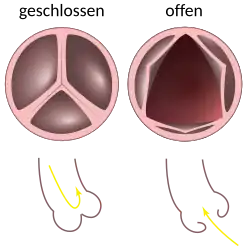

Die Aortenklappe (Valva aortae) ist eine der vier Herzklappen. Sie liegt in der Aortenöffnung (Ostium aortae), direkt am Ursprung der Aorta aus der linken Herzkammer und verhindert den Rückfluss des Blutes zu Beginn der Erschlaffungsphase (Diastole) des Herzens.

Die Aortenklappe besteht als Taschenklappe zumeist aus drei halbmondförmigen Taschen (Valvulae), die Bildungen der Intima (der innersten Schicht der Blutgefäße) sind:

Die Klappe liegt mit ihren Ausbuchtungen (Sinus) im Anfangsteil der aufsteigenden Aorta (Aorta ascendens). Auf Deutsch werden die Taschen entsprechend der Abgänge der beiden Herzkranzarterien aus den zugehörigen Sinus bezeichnet: rechtskoronare Tasche (am Abgang der rechten Herzkranzarterie), linkskoronare Tasche (am Abgang der linken Herzkranzarterie) und akoronare Tasche (Sinus ohne abgehende Herzkranzarterie). Die Aortenklappe bildet sich beim Menschen gemeinsam mit der Pulmonalklappe in der 5. bis 7. Woche der Embryonalentwicklung. Manchmal besteht die Aortenklappe nur aus zwei Taschenklappen.